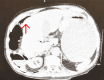

Small bowel obstruction (SBO) remains the most common diagnosis encountered by general surgeons, with 70% of cases related to adhesions from previous abdominal surgeries. Less common etiologies include Crohn's disease, gallstone ileus, and Meckel's diverticulum (MD). While MD is the most common congenital anomaly of the gastrointestinal tract, it is less frequently considered as a cause in adults. Nonetheless, it remains crucial to consider MD as a potential cause of SBO in adults, especially when evaluating patients with unexplained SBO and recurrent idiopathic abdominal pain, especially in those without a history of abdominal surgery. We present a case of a 74-year-old male presenting with right upper quadrant abdominal pain, constipation, and bilious vomiting, with a presumed diagnosis of SBO and perforation, potentially attributed to MD. This case highlights the differential challenges posed by small bowel diverticula and their complications, underscoring the need for vigilance in recognizing these complications and optimizing clinical management.